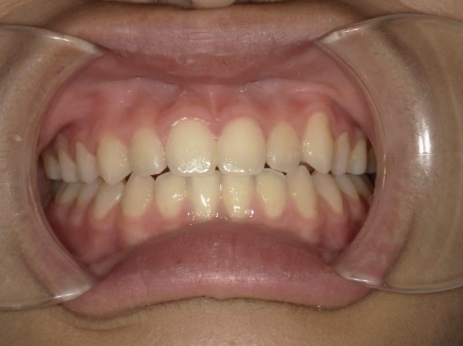

治療中⑥ 小6:11y8m

モノブロック装置継続中、左上八重歯の改善中